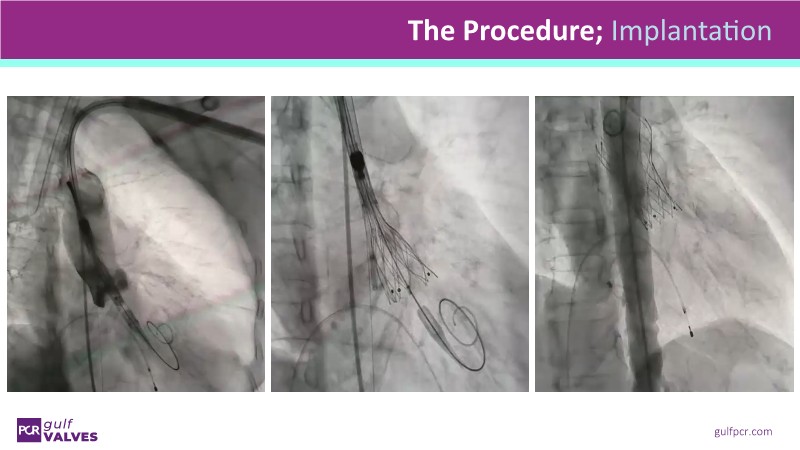

Discover a selection of cases showcasing the key features of the Navitor Valve System and its clinical applications. This session explores auxiliary access, the use of Navitor in alternative access and complex PCI, its performance in challenging peripheral anatomies, and innovative outcomes with the Vantage 30D system.